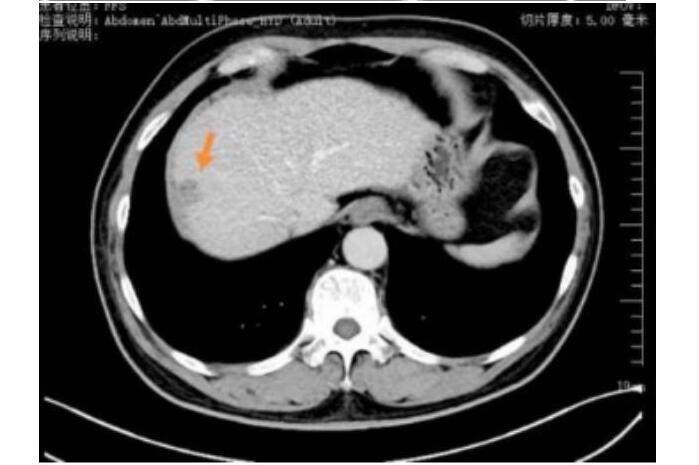

王先生(化名)65岁,2023年5月体检时发现肝占位,后行肝胆脾增强CT检查提示肝右叶富血供结节,径线约22mm*17mm,影像诊断考虑为肝恶性肿瘤,来到哈医大四院介入血管外科寻求进一步诊疗。患者行TACE术治疗后一周,接受了CT引导下冷冻消融治疗,术中患者疼痛轻微,术后患者恢复良好,三天后顺利出院。

TACE联合冷冻消融